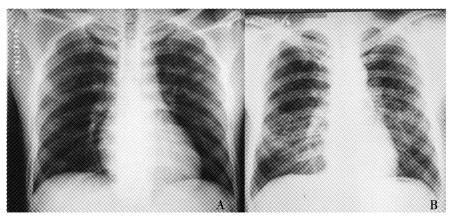

肺郎格罕细胞组织细胞增多症1例